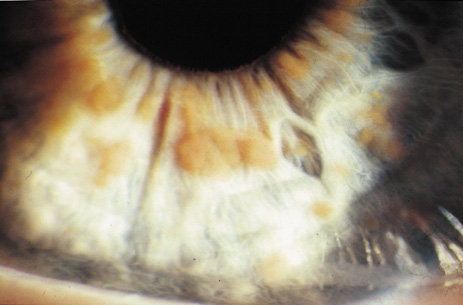

Lisch nodules are hamartomas (a tumor involving only those tissue elements normally found at the involved site) of the iris pigment epithelium. They are dome-shaped discrete lesions, are typically light brown in color, and may also be found in the angle.38 Lisch nodules appear earlier (33% at 2.5 years, 50% at 5 years of age)39 than neurofibromas. They are benign and can help to confirm diagnosis in children who may have café au lait spots as the only other clinical finding. Lisch nodules are present in nearly all adults with NF139,40 but are rare in NF2 (Fig. 3).41,42 Diffuse nodular iris nevi (also known as iris mamillations) should not be confused with Lisch nodules. Its clinical significance is not well established.43,44

- At least two Lisch nodules (Fig. 3)